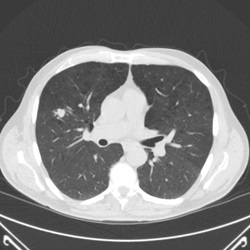

The gold standard for identifying lung cancer early uses computed tomography (CT) scans. Henry Ford Health was part of a national study that found CT lung screening reduced the chance of dying from lung cancer by 20 percent, compared with chest X-ray screening.

The CT scan is quick and painless. It uses a combination of X-rays and computer technology to create detailed images. You don’t have to worry about receiving too much radiation during screening. Our low-dose CT scan technology means you’ll experience about a quarter of the radiation emitted by standard CT scans.

Lung cancer can be revealed by a low-dose computed tomography (LDCT) screening.